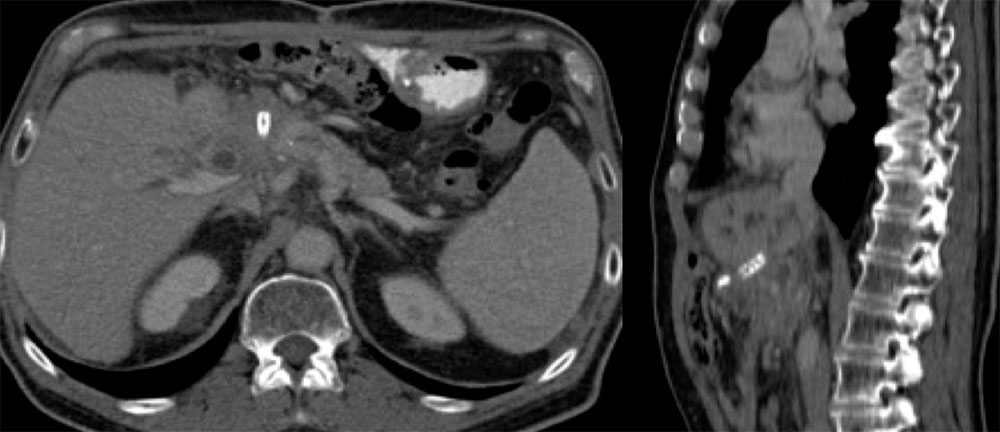

Case 12  67 year old man w/ampullary adenocarcinoma, status post whipple complicated by gastroduodenal artery hemorrhage necessitating hepatic artery stent. CT performed for follow up showed interval increase in biliary obstruction, narrowing of the portal vein confluence, concerning for recurrent tumor Axial CT and sagittal MPR demonstrate:

|

Case 12  67 year old man w/ampullary adenocarcinoma, status post whipple complicated by gastroduodenal artery hemorrhage necessitating hepatic artery stent. CT performed for follow up showed interval increase in biliary obstruction, narrowing of the portal vein confluence, concerning for recurrent tumor Axial CT and sagittal MPR demonstrate:

|

Migrated Hepatic Artery Stent

|

Migrated Hepatic Artery Stent

|